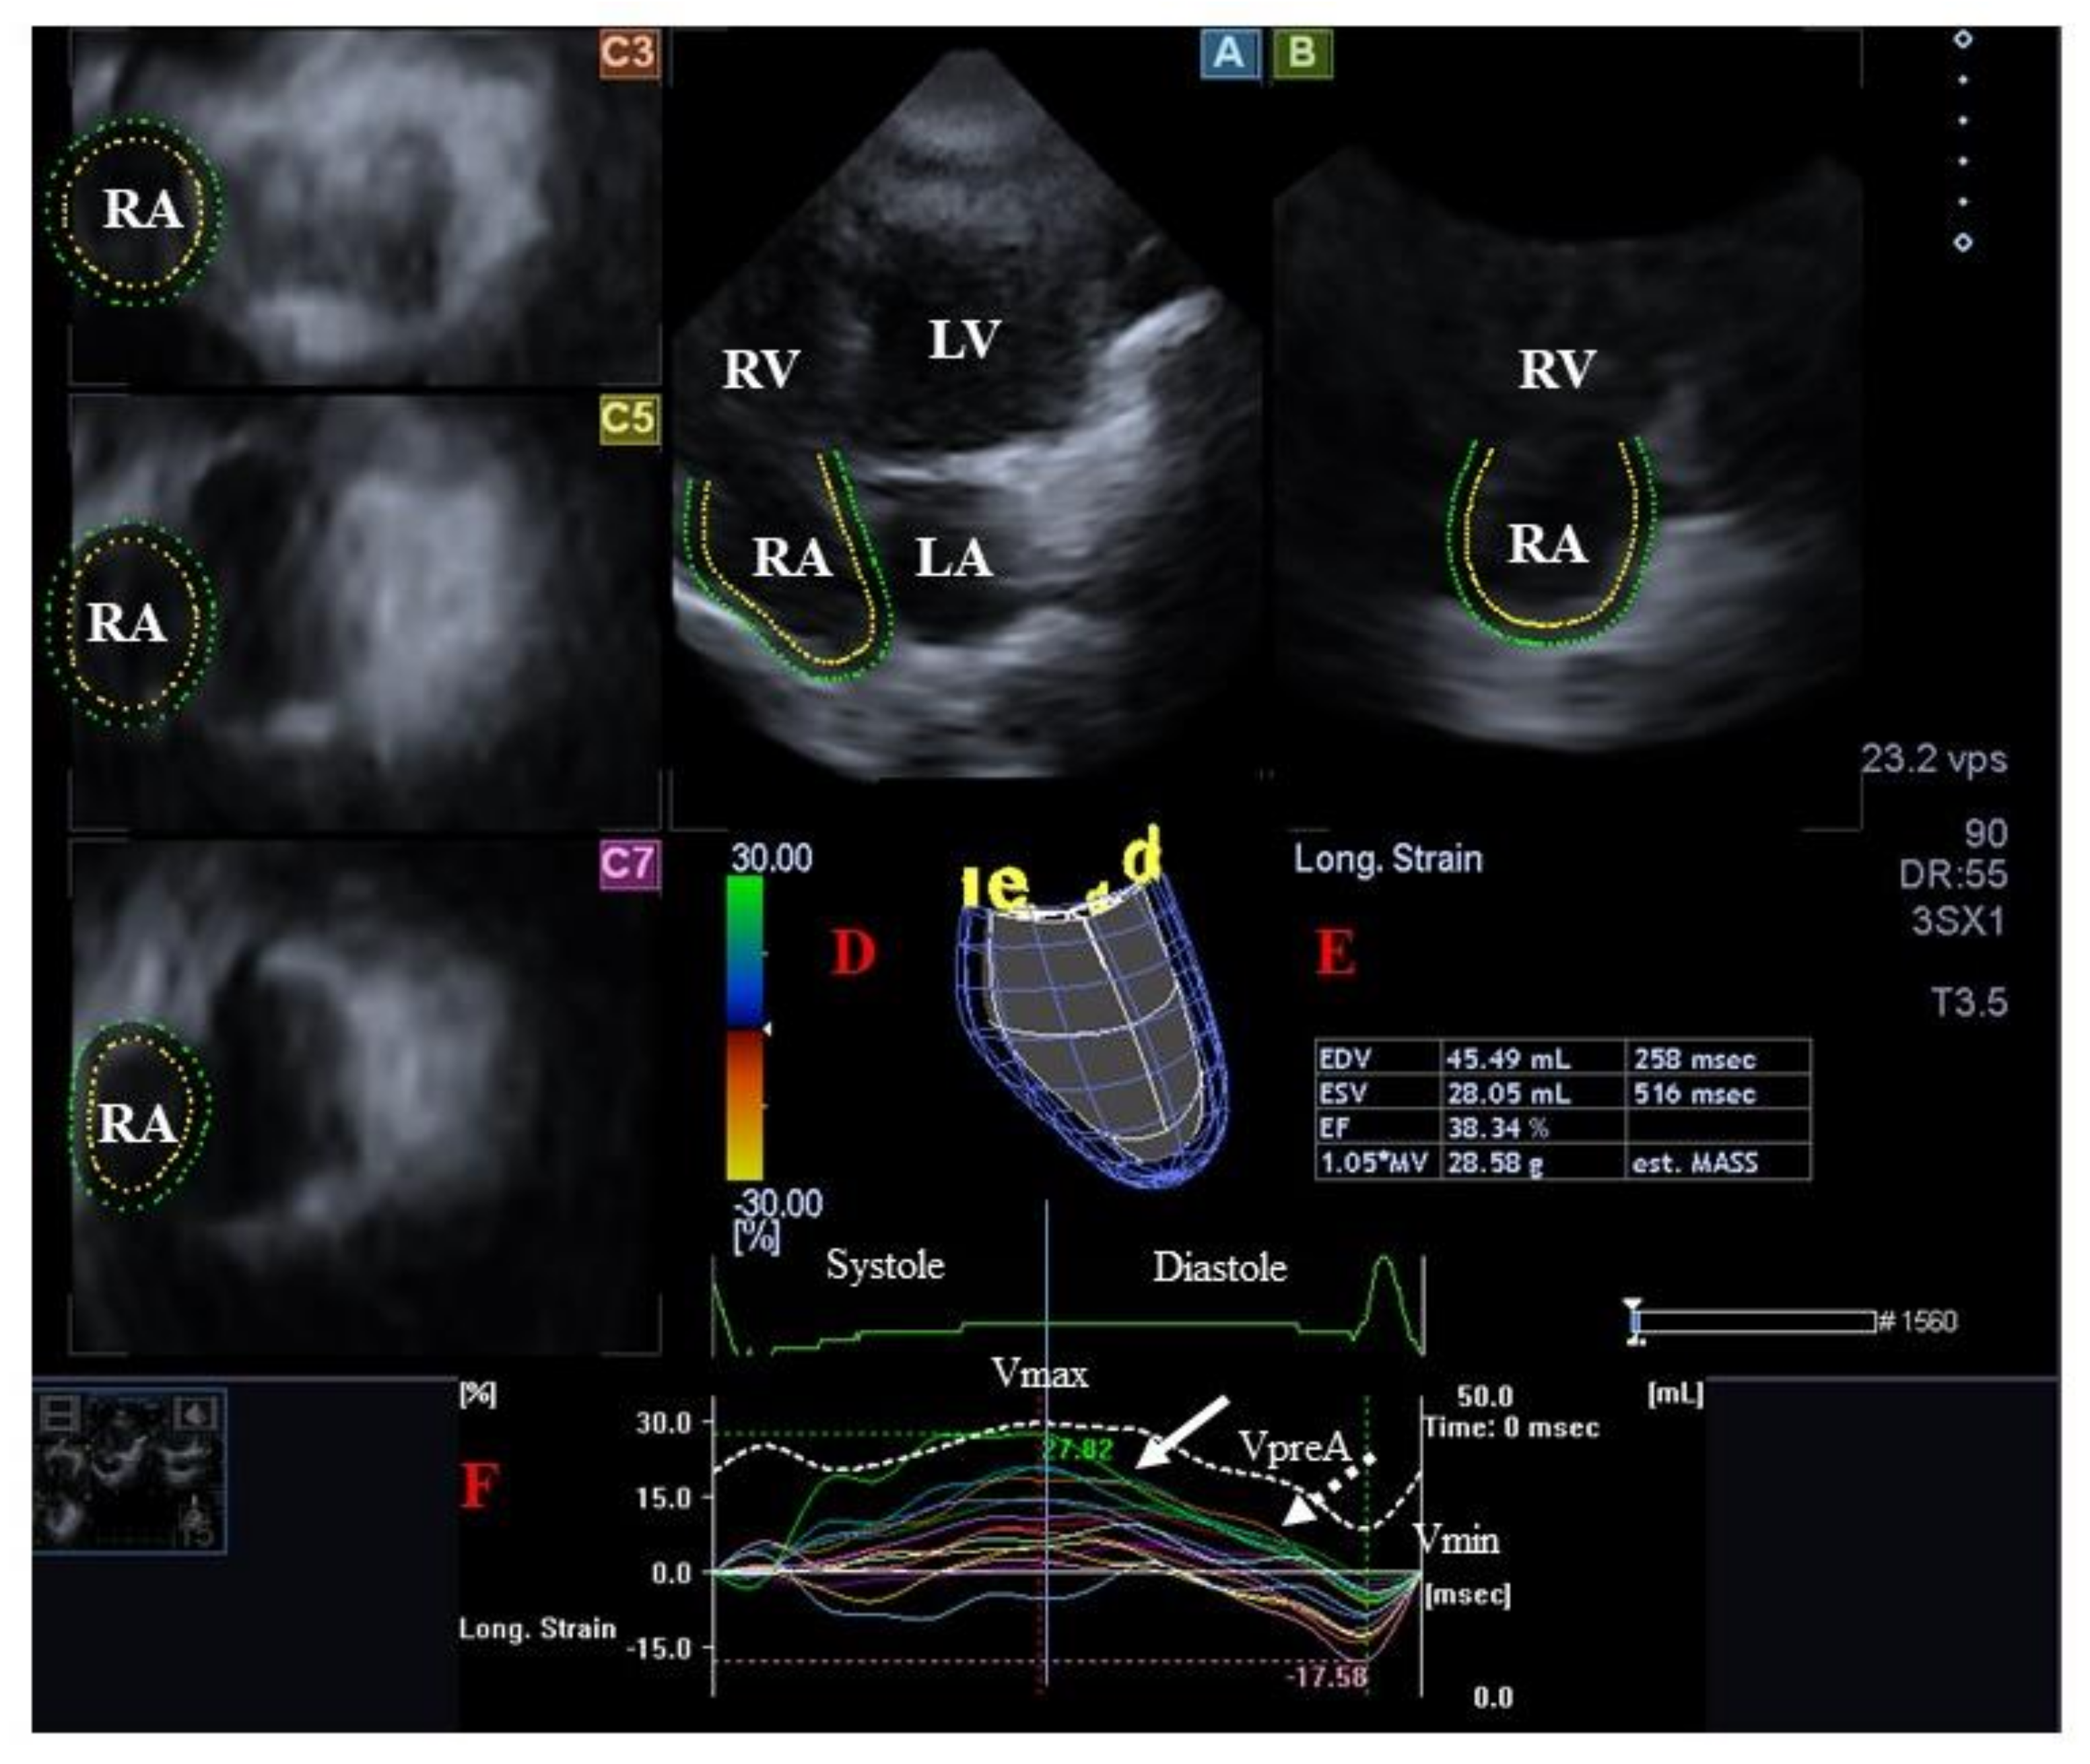

- Kormányos, Á.; Kalapos, A.; Domsik, P.; Gyenes, N.; Ambrus, N.; Valkusz, Z.; Lengyel, C.; Nemes, A. The right atrium in acromegaly-a three-dimensional speckle-tracking echocardiographic analysis from the MAGYAR-Path Study. Quant. Imaging Med. Surg. 2020, 10, 646–656. [Google Scholar] [CrossRef] [PubMed]